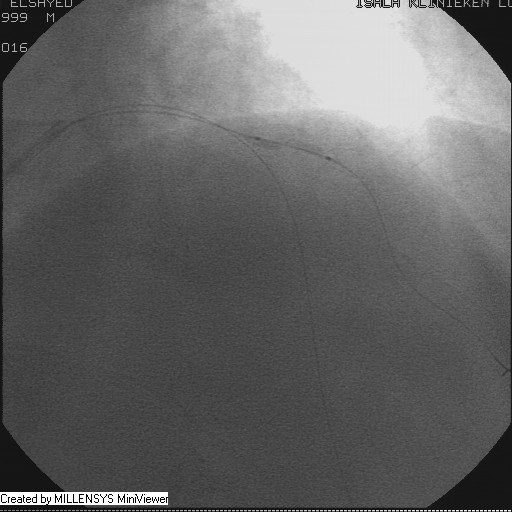

Patient transfered to Cardiac Catheterization Laboratory, coronary angiography showed atherosclerotic coronaries but without significant lesions, especially LAD that was patent with TIMI 3 flow (Figure 1- 5). Re-evaluation of the Angiography showed a small stump that can be for an occluded 1st diagonal (Figure 2a), at that level the LAD has a non-significant lesion.

Figure 5